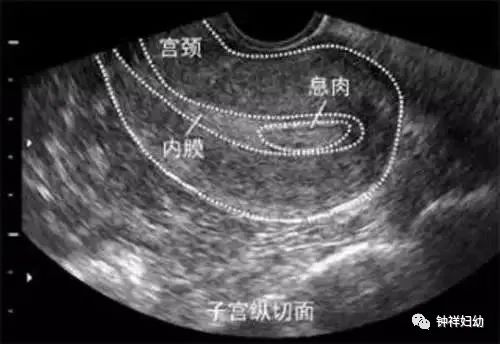

1、超声检查:是最常用的子宫内膜息肉检查方法,已婚或有性生活者首选经阴道超声检查。超声检查的最佳时间为增殖期(月经第5-14天)。

2、宫腔镜检查及病理组织学诊断:宫腔镜检查及镜下切除内膜息肉行病理学检查是诊断子宫内膜息肉的金标准。